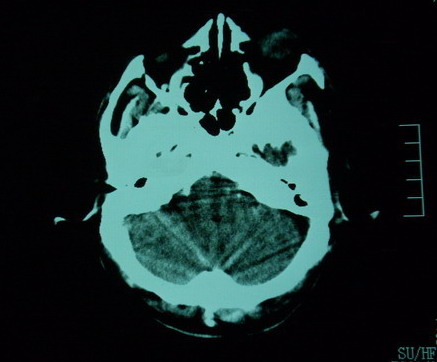

男,70岁,左侧肢体活动障碍口角向右侧歪斜2天,有高bp病史

pe:神情,能与之正常交流,吐字不清,180/90mmhg,双瞳孔无异常,左侧肢体肌力1级 b(+)

图中有个同心圆壮低密度影是ct伪影,见笑了。

1、右侧基底区及外囊区腔隙性脑梗塞。2、脑萎缩。

右基底节内囊前支区腔隙性脑梗塞,脑萎缩

右基底节区脑强隙 右基底节区低密度影密度太低 边界清 不会是2天的梗赛灶

2天左右的腔隙性脑梗死ct多难以发现 何况你的机器又差 很难显示 即使显示密度应该略低影

边缘模糊